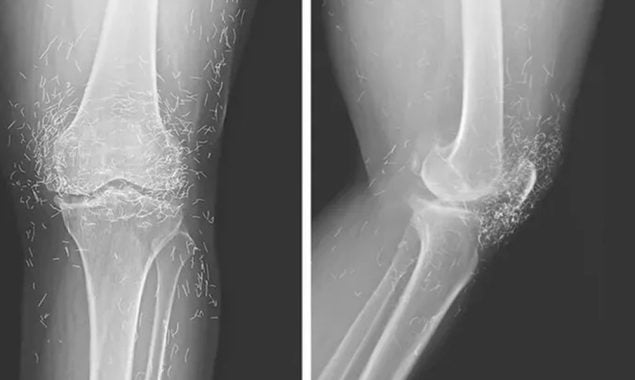

یہ گھٹنا ہے یا ستاروں کا جھرمٹ : ڈاکٹرز نے ایکسرے دیکھ کر سر پکڑ لیا

خبر رساں ادارے کی رپورٹ کے مطابق قبل ازیں اوسٹیو آرتھرائٹس یعنی جوڑوں میں شدید درد کی شکایت پر جب اس خاتون معائنہ کیا گیا تو تصویر میں سینکڑوں باریک سنہری دھاگے چمکتے دکھائی دیے۔

ایکسرے کرنے پر ڈاکٹرز کو رپورٹ میں گھٹنے کی ہڈی کے اندرونی حصے میں سختی اور گاڑھا پن، اور ہڈیوں کی غیر معمولی نشوونما نظر آئی، یہ سب اوسٹیو آرتھرائٹس کی عام علامات تھیں۔

لیکن ساتھ ہی گھٹنوں کے اردگرد کے ٹشوز میں سینکڑوں ننھے سونے کے دھاگے بھی موجود دکھائی دیے۔